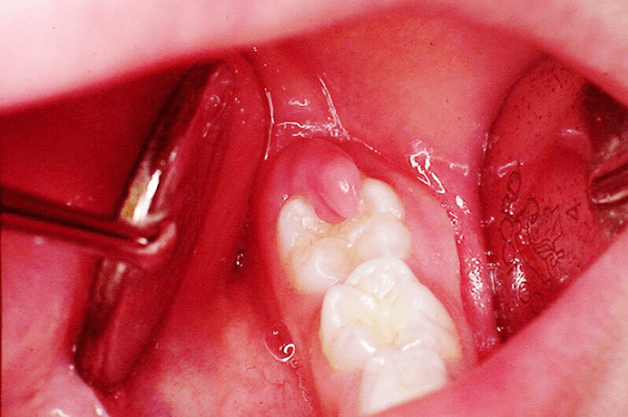

Viêm lợi trùm là tình trạng mô nướu bị viêm, sưng tấy và che phủ lên bề mặt của răng. Tình trạng này thường gặp ở phần răng hàm dưới và xung quanh răng khôn. Viêm lợi trùm có thể hình thành ngay khi răng khôn chỉ nhú lên 1 phần. Nếu tình trạng này không được xử lý kịp thời thì có thể xảy ra tình trạng nhiễm trùng lan rộng sang các bộ phận khác, khó mở miệng khi nhai cắn và làm hạn chế ăn uống, đe dọa đến tính mạng khi nhiễm trùng độc đi vào đường máu và lan ra toàn thân.

Tiểu phẫu cắt bỏ lợi

Nếu lợi trùm răng gây đau nhức hoặc tái phát thường xuyên thì phải tiến hành phẫu thuật cắt bỏ vạt nước hoặc răng khôn.